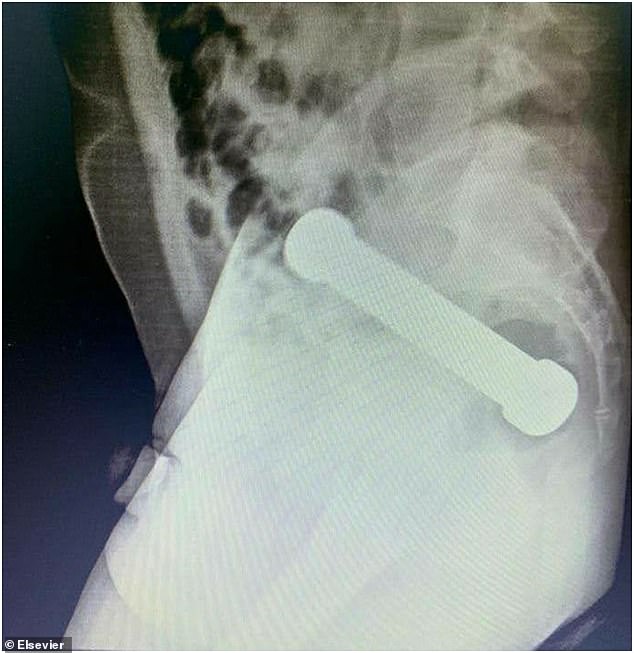

Nachdem eine Untersuchung seiner rektalen Region keine Anzeichen dafür ergab, was seine Symptome verursachen könnte, ordneten die Ärzte eine Röntgenaufnahme seines Unterleibs an.

Das Röntgenbild zeigte eine Hantel, die fast 20 cm lang war und dort steckte, wo der Dickdarm auf das Rektum trifft.